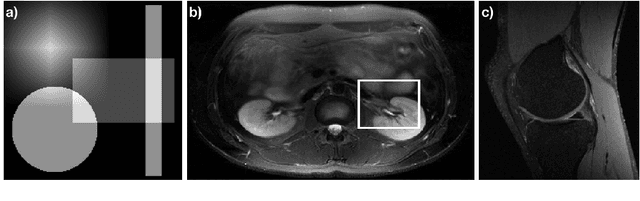

Abstract:The Gridding algorithm has shown great utility for reconstructing images from non-uniformly spaced samples in the Fourier domain in several imaging modalities. Due to the non-uniform spacing, some correction for the variable density of the samples must be made. Existing methods for generating density compensation values are either sub-optimal or only consider a finite set of points (a set of measure 0) in the optimization. This manuscript presents the first density compensation algorithm for a general trajectory that takes into account the point spread function over a set of non-zero measure. We show that the images reconstructed with Gridding using the density compensation values of this method are of superior quality when compared to density compensation weights determined in other ways. Results are shown with a numerical phantom and with magnetic resonance images of the abdomen and the knee.